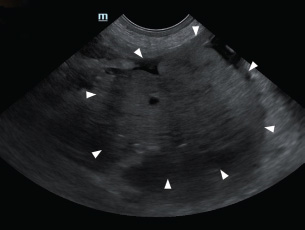

To correct hypovolemic shock prior to surgery, lactated Ringer’s solution was administered intravenously (IV) at a rate of 90 ml/kg/hour. Additionally, one unit of whole blood was transfused to restore circulating volume. Premedication consisted of butorphanol (0.2 mg/kg IV; Butophan Inj., Myungmoon Pharm. Co., Ltd., Seoul, Republic of Korea) and cefazolin (30 mg/kg IV; Safdin, Daehan New Pharm Co., Ltd, Republic of Korea). Anesthesia was induced with propofol (6 mg/kg IV; Provive 1%, Myungmoon Pharm. Co., Ltd., Seoul, Republic of Korea) and maintained with 1.2%–1.4% isoflurane (Forane sol., Choongwae. Co., Ltd., Seoul, Republic of Korea) delivered in 100% oxygen. Lactated Ringer’s solution was administered at 10 ml/kg/hour IV throughout the surgical procedure. Exploratory laparotomy via a ventral midline incision confirmed the presence of hemoperitoneum (Fig. 3). A firm, round, lobulated mass measuring 6 cm in height, 7 cm in width, and 8.5 cm in length was identified in the right pancreatic lobe. The mass was firmly adhered to the jejunal mesentery and adjacent mesenteric vessels (Fig. 4), consistent with its location in the caudal portion of the right pancreatic limb. Active bleeding was observed from a pancreatic vessel adjacent to the mass (Fig. 5). Blunt dissection with moistened cotton swabs was used to separate the right lobe from surrounding vessels. The pancreatic vessels were ligated using a bipolar vessel-sealing device (LigaSure; Valleylab, Tyco Healthcare Group, Boulder, CO, USA). A ligature was placed approximately 2 cm proximal to the tumor within the pancreatic parenchyma, and a portion of normal pancreas was excised. Approximately 13 cm of jejunum and the associated mesentery were also resected, followed by an end-to-end jejunal anastomosis. No gross metastatic lesions were observed in the liver or spleen. All excised tissues were fixed in 10% buffered formalin for histopathological examination.

Fig. 4. During exploratory laparotomy, a firm, round, and lobulated mass approximately 6 cm in height, 7 cm in width, and 8.5 cm in length (black arrowhead) was found in the right lobe of the pancreas. This mass strongly adhered to the jejunal mesentery and mesenteric vessels.